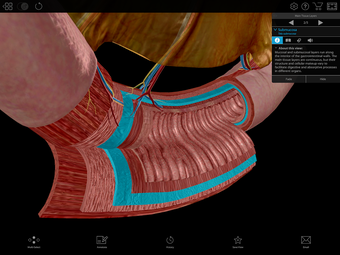

Physiology & Pathology is a comprehensive application that provides an interactive guide to human anatomy. Developed by Visible Body, this Android application is a full version licensed program that falls under the lifestyle category of medical subcategories. With more than 5,800 3D models, 38 animations, 16 illustrations, and 26 quizzes, this application covers 48 physiology topics and 57 conditions, allowing users to explore the step-by-step breakdown of common cardiovascular, renal, respiratory, gastrointestinal, and musculoskeletal processes.

One of the most remarkable features of this application is that it enables users to compare 3D models of normal anatomy with models of common diseases and conditions. Furthermore, users can set the heart rate and visualize conduction in a dissectable, beating 3D heart while following along on an ECG. The application also presents animations that demonstrate the physiological processes of gas exchange, pulmonary ventilation, fluid balance, peristalsis, and more. Interactive lessons walk users through the progression of atherosclerosis, kidney stones, lung cancer, and other common conditions, and quizzes test users' knowledge of various physiological processes and pathologies.